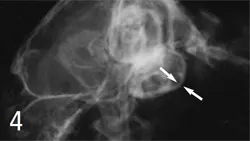

4. Feline Tympanic Bulla: Otitis Media: Bulla in a case of otitis media in a cat shows thickening of wall (arrows) and more generalized increase in opacity.